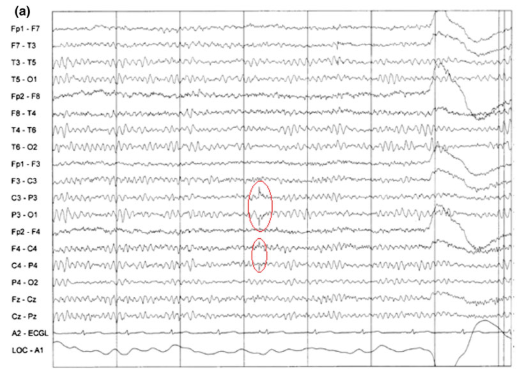

4

Q

A

Myogenic artifact